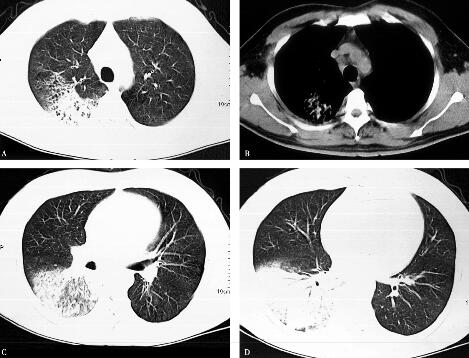

6.胸部影像学:右肺多叶、多段片状浸润性阴影,有实变,右胸腔有少量胸腔积液(图1)。

图1

具有临床意义的检查结果有:①血常规示白细胞计数、中性粒细胞百分比均增高; C-反应蛋白,降钙素原显著升高;②胸部影像学示右肺多发浸润影;③动脉血氧分压降低。结合患者的病史和体格检查结果,进一步支持感染性疾病—社区获得性肺炎(community acquired pneumonia,CAP)的诊断。动脉血氧分压降低考虑因肺部大面积炎性病变进而影响气体交换所致。进一步的处理应是立即选择合适的抗感染药物进行治疗。